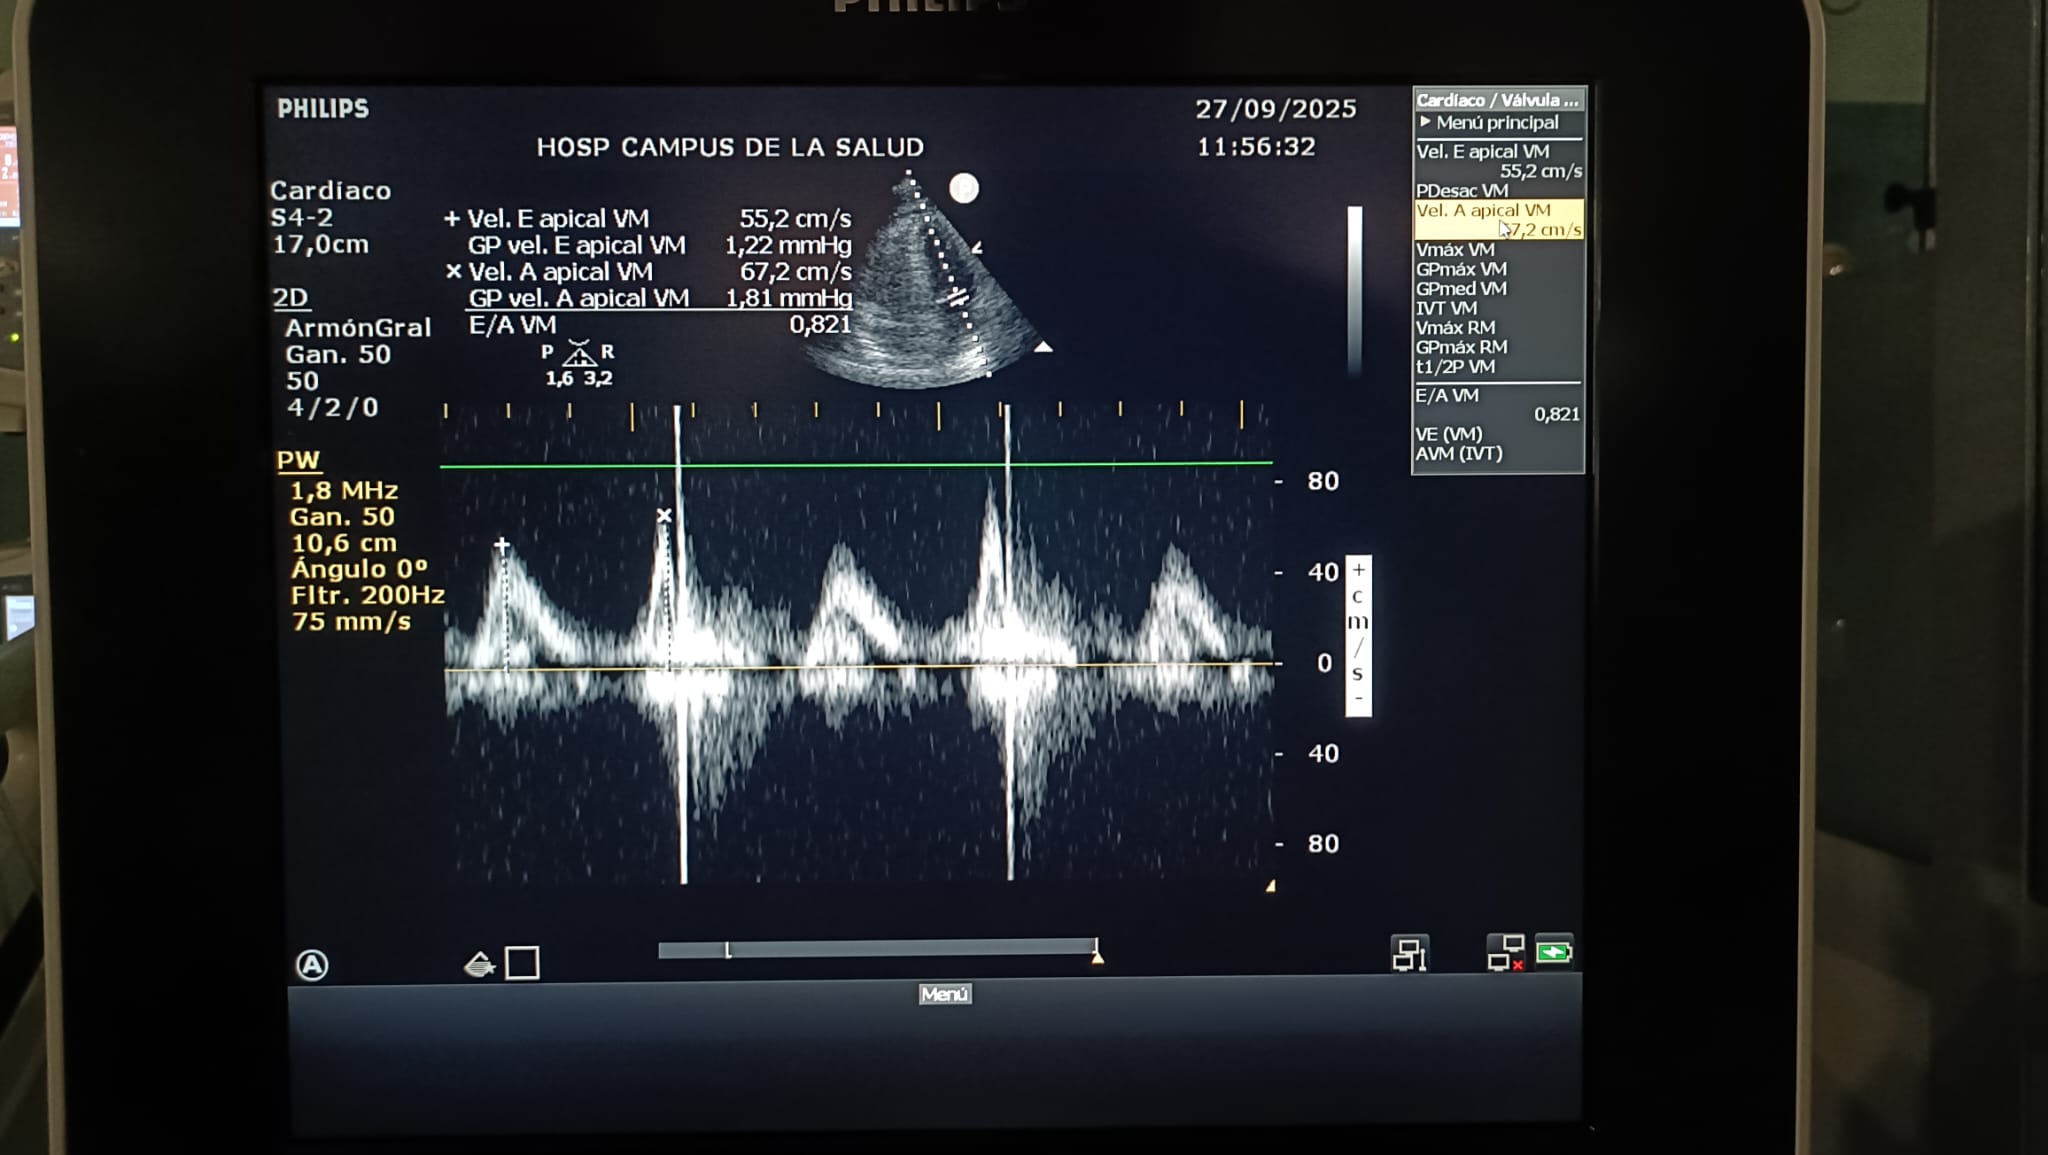

Relación E/A: 0.821

Relación E/E' lateral: 6.76